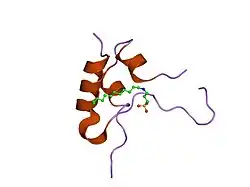

IGF-1 is a protein that in humans is encoded by the IGF1 gene.[8][9] IGF-1 consists of 70 amino acids in a single chain with three intramolecular disulfide bridges. IGF-1 has a molecular weight of 7,649 daltons.[10] In dogs, an ancient mutation in IGF1 is the primary cause of the toy phenotype.[11]

![3lri: Solution structure and backbone dynamics of long-[Arg(3)]insulin-like growth factor-I](./_assets_/PDB_3lri_EBI.jpg)